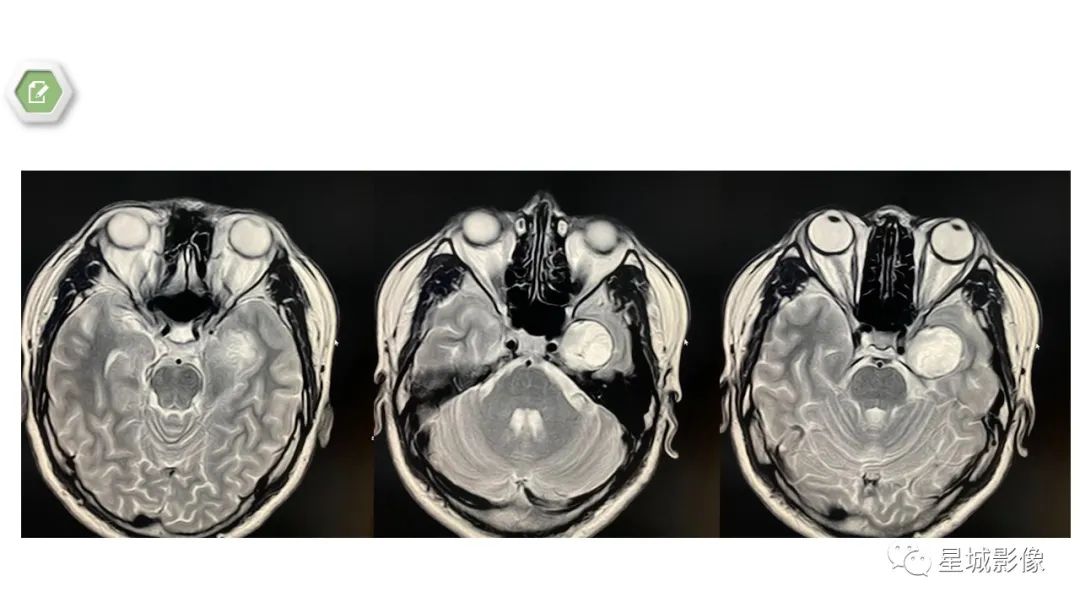

【病例】颅内成熟性囊性畸胎瘤1例MR影像表现-2